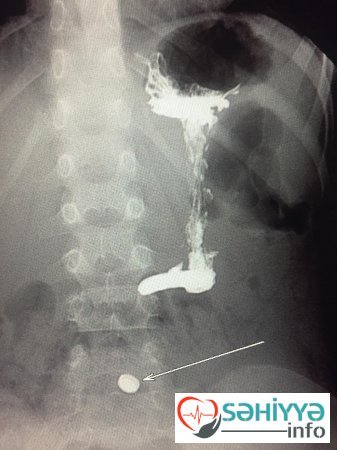

Sehiyye.info xəbər verir ki,Lent.az-ın məlumatına görə, paytaxtda yerləşən özəl xəstəxanalardan birinə gətirilən 4 yaşlı uşağın nazik bağırsağında metal yad cisim tapılıb. Uşağın müayinəsi zamanı həkimləri heyrətə gətirən fakt ortaya çıxıb.

Belə ki, həmin azyaşlının nazik bağırsağında batareya aşkarlanıb. İlkin məlumata görə, azyaşlının həmin batareyanı udduğu ehtimal edilir.